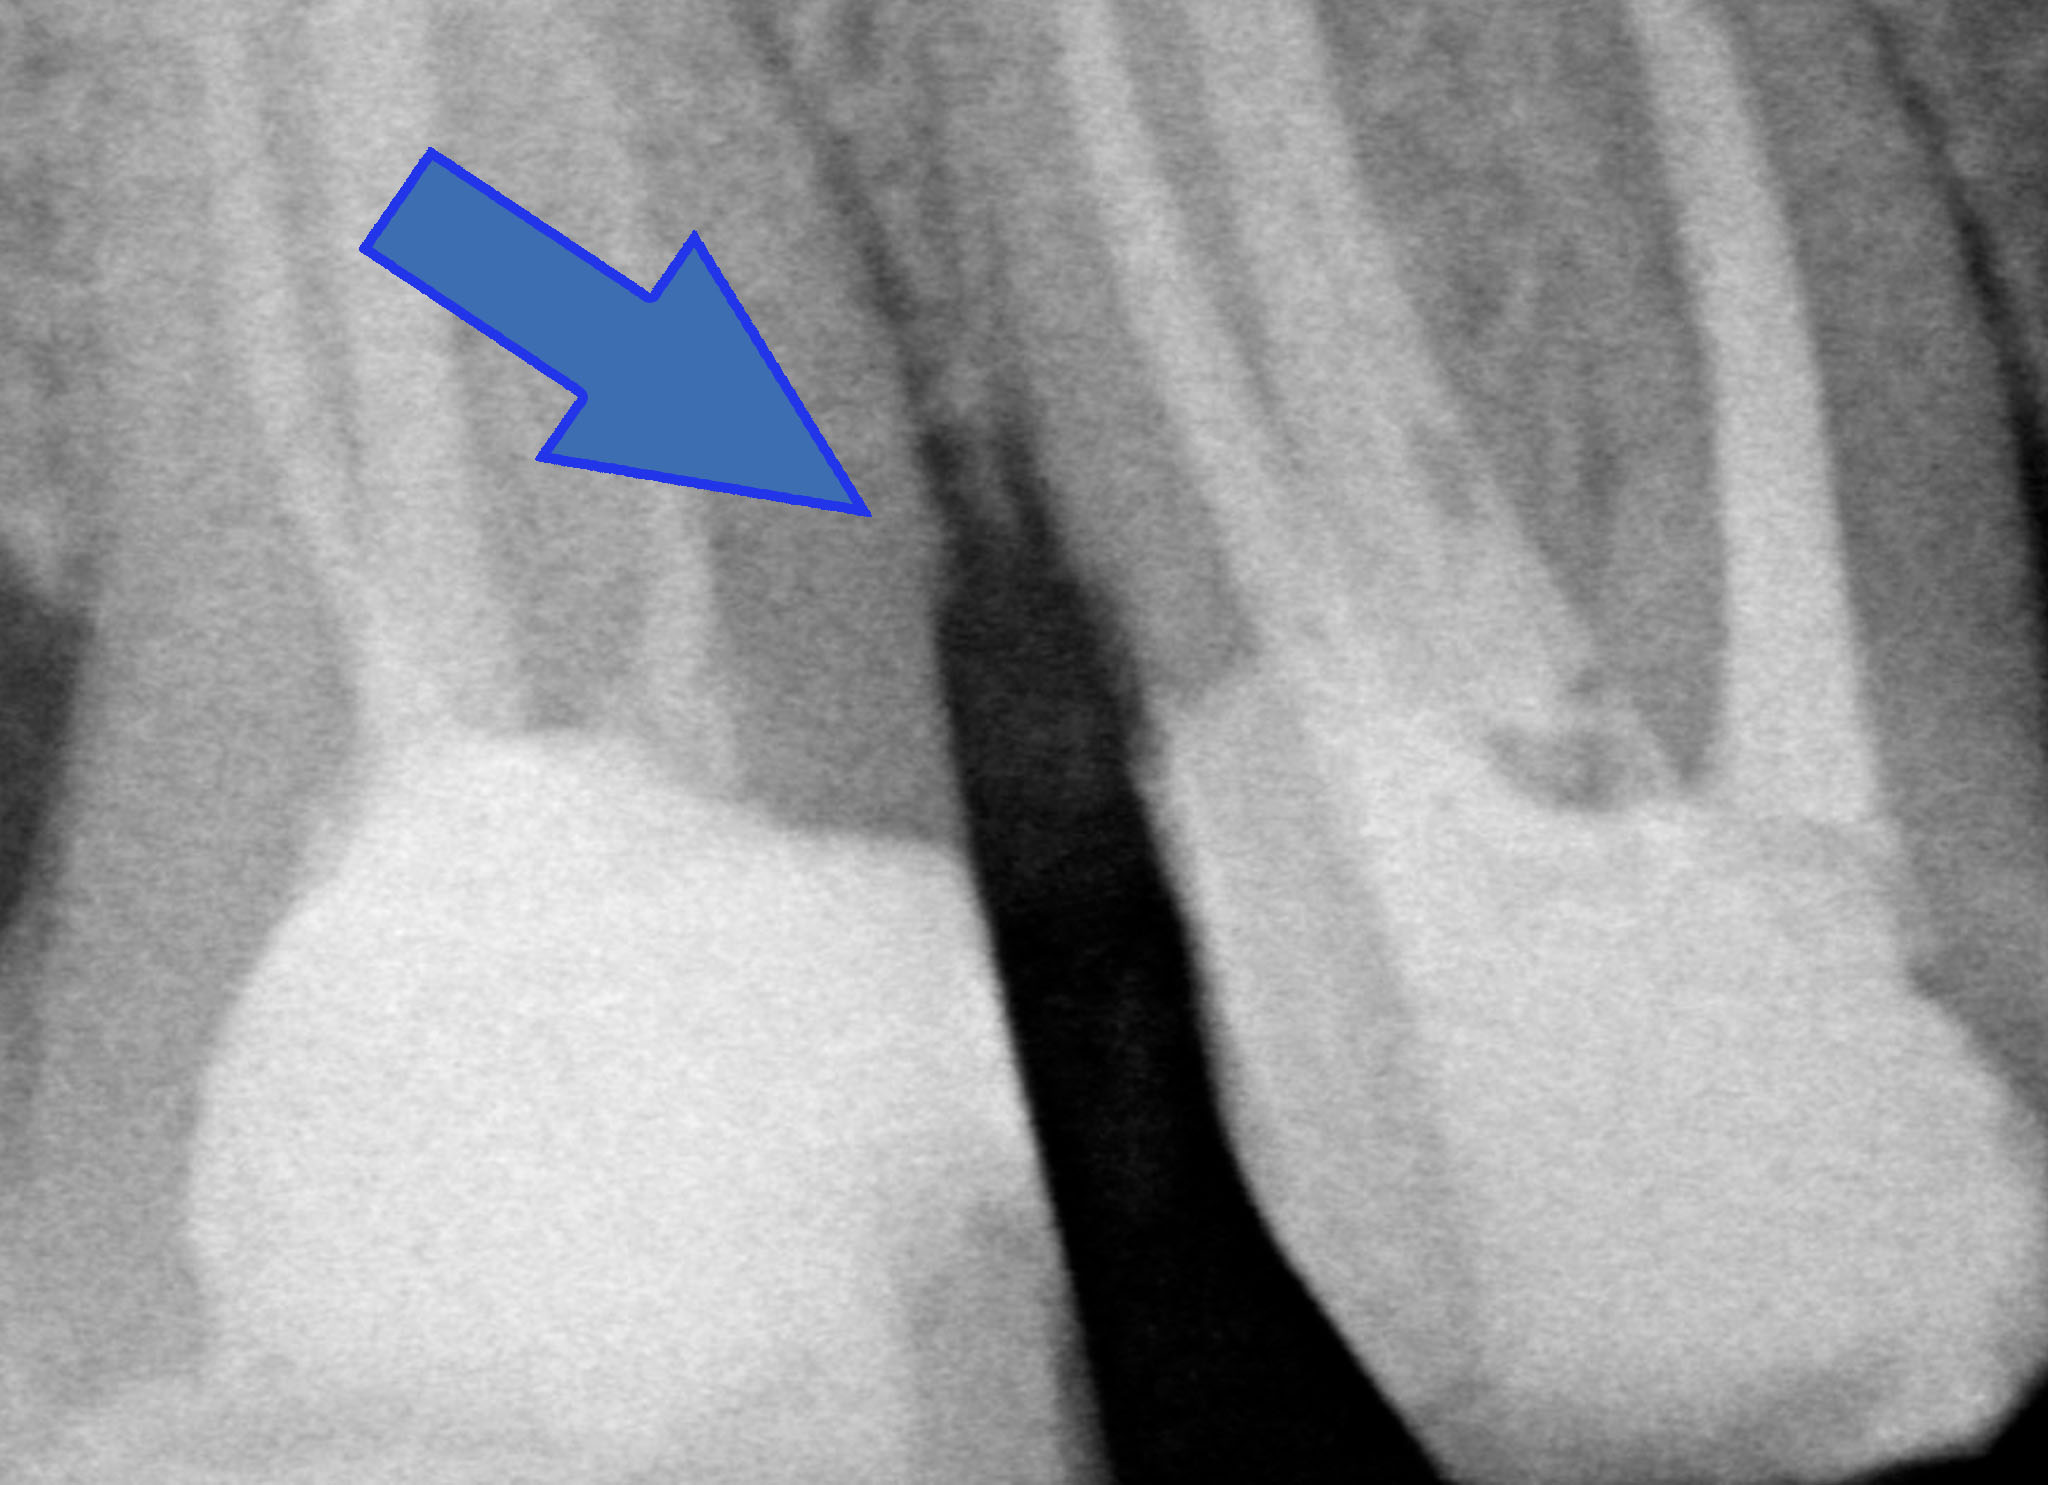

Accademicamente potremmo dire: CARIE SECONDARIA A CARICO DI 1.6 PRECEDENTEMENTE RESTAURATO MEDIANTE CORONA IN METALLO CERAMICA.

Ma io nella mia testa dico “chi ha fatto quella corona avrebbe dovuto fare un allungamento di corona clinica, ma non lo sapeva o non lo voleva fare. Quindi non ha potuto gestire correttamente il margine di chiusura distale. Quindi è rimasto del tessuto cariato o non è stato effettuato un corretto sigillo marginale per cui… E’ SUCCESSO IL FATTACCIO!”

Anche se il paziente non avvertiva nessun fastidio abbiamo fatto una visita completa, che comprende le due bite-wings posteriori e ci siamo accorti del problema. Ora però lo dobbiamo risolvere. Abbiamo tre strade: